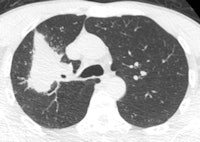

A 50-year old male patient with NSCLC stage pT2b pN2 cM0, imaged with FDG-PET/CT-MR. On coronal PET maximum intensity projection (MIP) image, an FDG-avid tumor in the right upper lobe and a mediastinal lymph node metastasis are seen. All images courtesy of Dr. Martin Huellner.For many years, PET/CT has been the standard modality for staging NSCLC patients. So, before PET/MRI can supplant it for this application, some basic clinical questions need to be addressed, said lead author Dr. Martin Huellner from University Hospital Zurich.

The imaging protocol consisted of whole-body PET/CT-MR (Discovery 690, GE Healthcare, 3-tesla MRI system MR 750w, GE). The MRI protocol included whole-body coronal short-tau inversion recovery (STIR) for eight minutes, followed by axial whole-body LAVA-Flex acquisition for three minutes and thoracic axial periodically rotated overlapping parallel lines with enhanced reconstruction (PROPELLER) imaging for five minutes. Total MRI acquisition time was approximately 16 minutes.